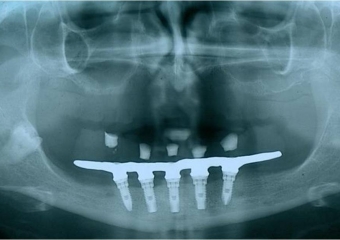

Raio x final